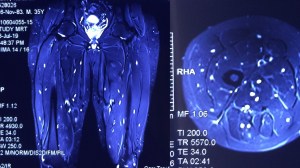

Disseminated cysticercosis (tapeworm) in a vegetarian male

A 35-year-old vegetarian man presented with a generalized convulsion. MRI brain showed extensive cysticerci lesions involving the bilateral supra and infra-tentorial brain parenchyma, myofascial planes of the face, neck, floor of mouth, parotid glands and left orbital extraocular muscles (figure 1). MRI thigh showed diffuse cysticerci involving multiple muscles (figure 2). Disseminated cysticercosis can occur in vegetarians and non-pork eaters due to fecal-oral contamination of food with Taenia solium eggs from tapeworm carriers1.